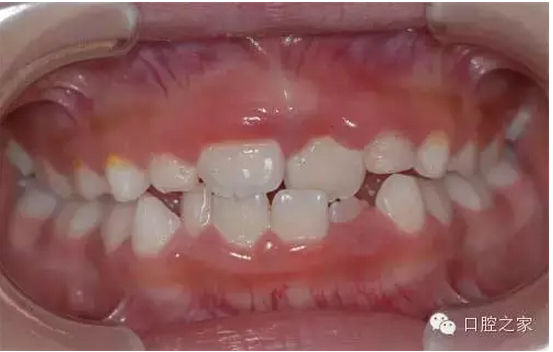

疾病概述

上下牙弓近遠中關系異??杀憩F(xiàn)為下頜前突,近中錯合及前牙反合。多由于不良哺乳姿勢,乳前牙滯留或早失,上恒切牙先天性缺失,不良習慣、乳尖牙磨耗不足,全身性疾病以及遺傳性下頜前突所致。因程度不同可表現(xiàn)為前牙反合,磨牙為中性合,嚴重病例則前牙反合、后牙近中合及下頜前突同時存在。

QQ圖片20150803104838.png

臨床表現(xiàn)

前牙反,顏面可表現(xiàn)為下頜前突,上頜發(fā)育不足的凹形側面形。